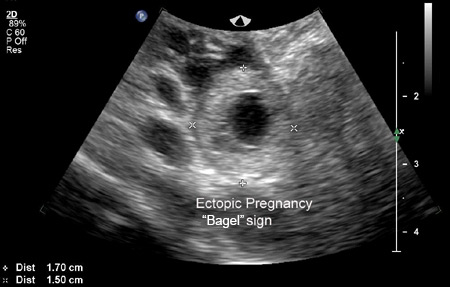

A gravidez ectópica é visualizada na USTV, e o diagnóstico é feito de maneira direta.[Figure caption and citation for the preceding image starts]: Imagem de ultrassonografia de gravidez ectópica demonstrando sinal de "rosquinha"Do acervo da Dr. Melissa Fries; usado com permissão [Citation ends].

[Figure caption and citation for the preceding image starts]: Imagem de ultrassonografia de gravidez ectópica demonstrando sinal de "rosquinha"Do acervo da Dr. Melissa Fries; usado com permissão [Citation ends].

Uma massa anexial movendo-se separadamente para o ovário, às vezes chamada de "sinal deslizante", com um saco gestacional vazio, às vezes descrito como um "anel tubário" ou "sinal em forma de anel", e uma massa anexial complexa, não homogênea, movendo-se separada para o ovário, são altamente sugestivos de uma gravidez ectópica, mas não diagnóstico.[62]